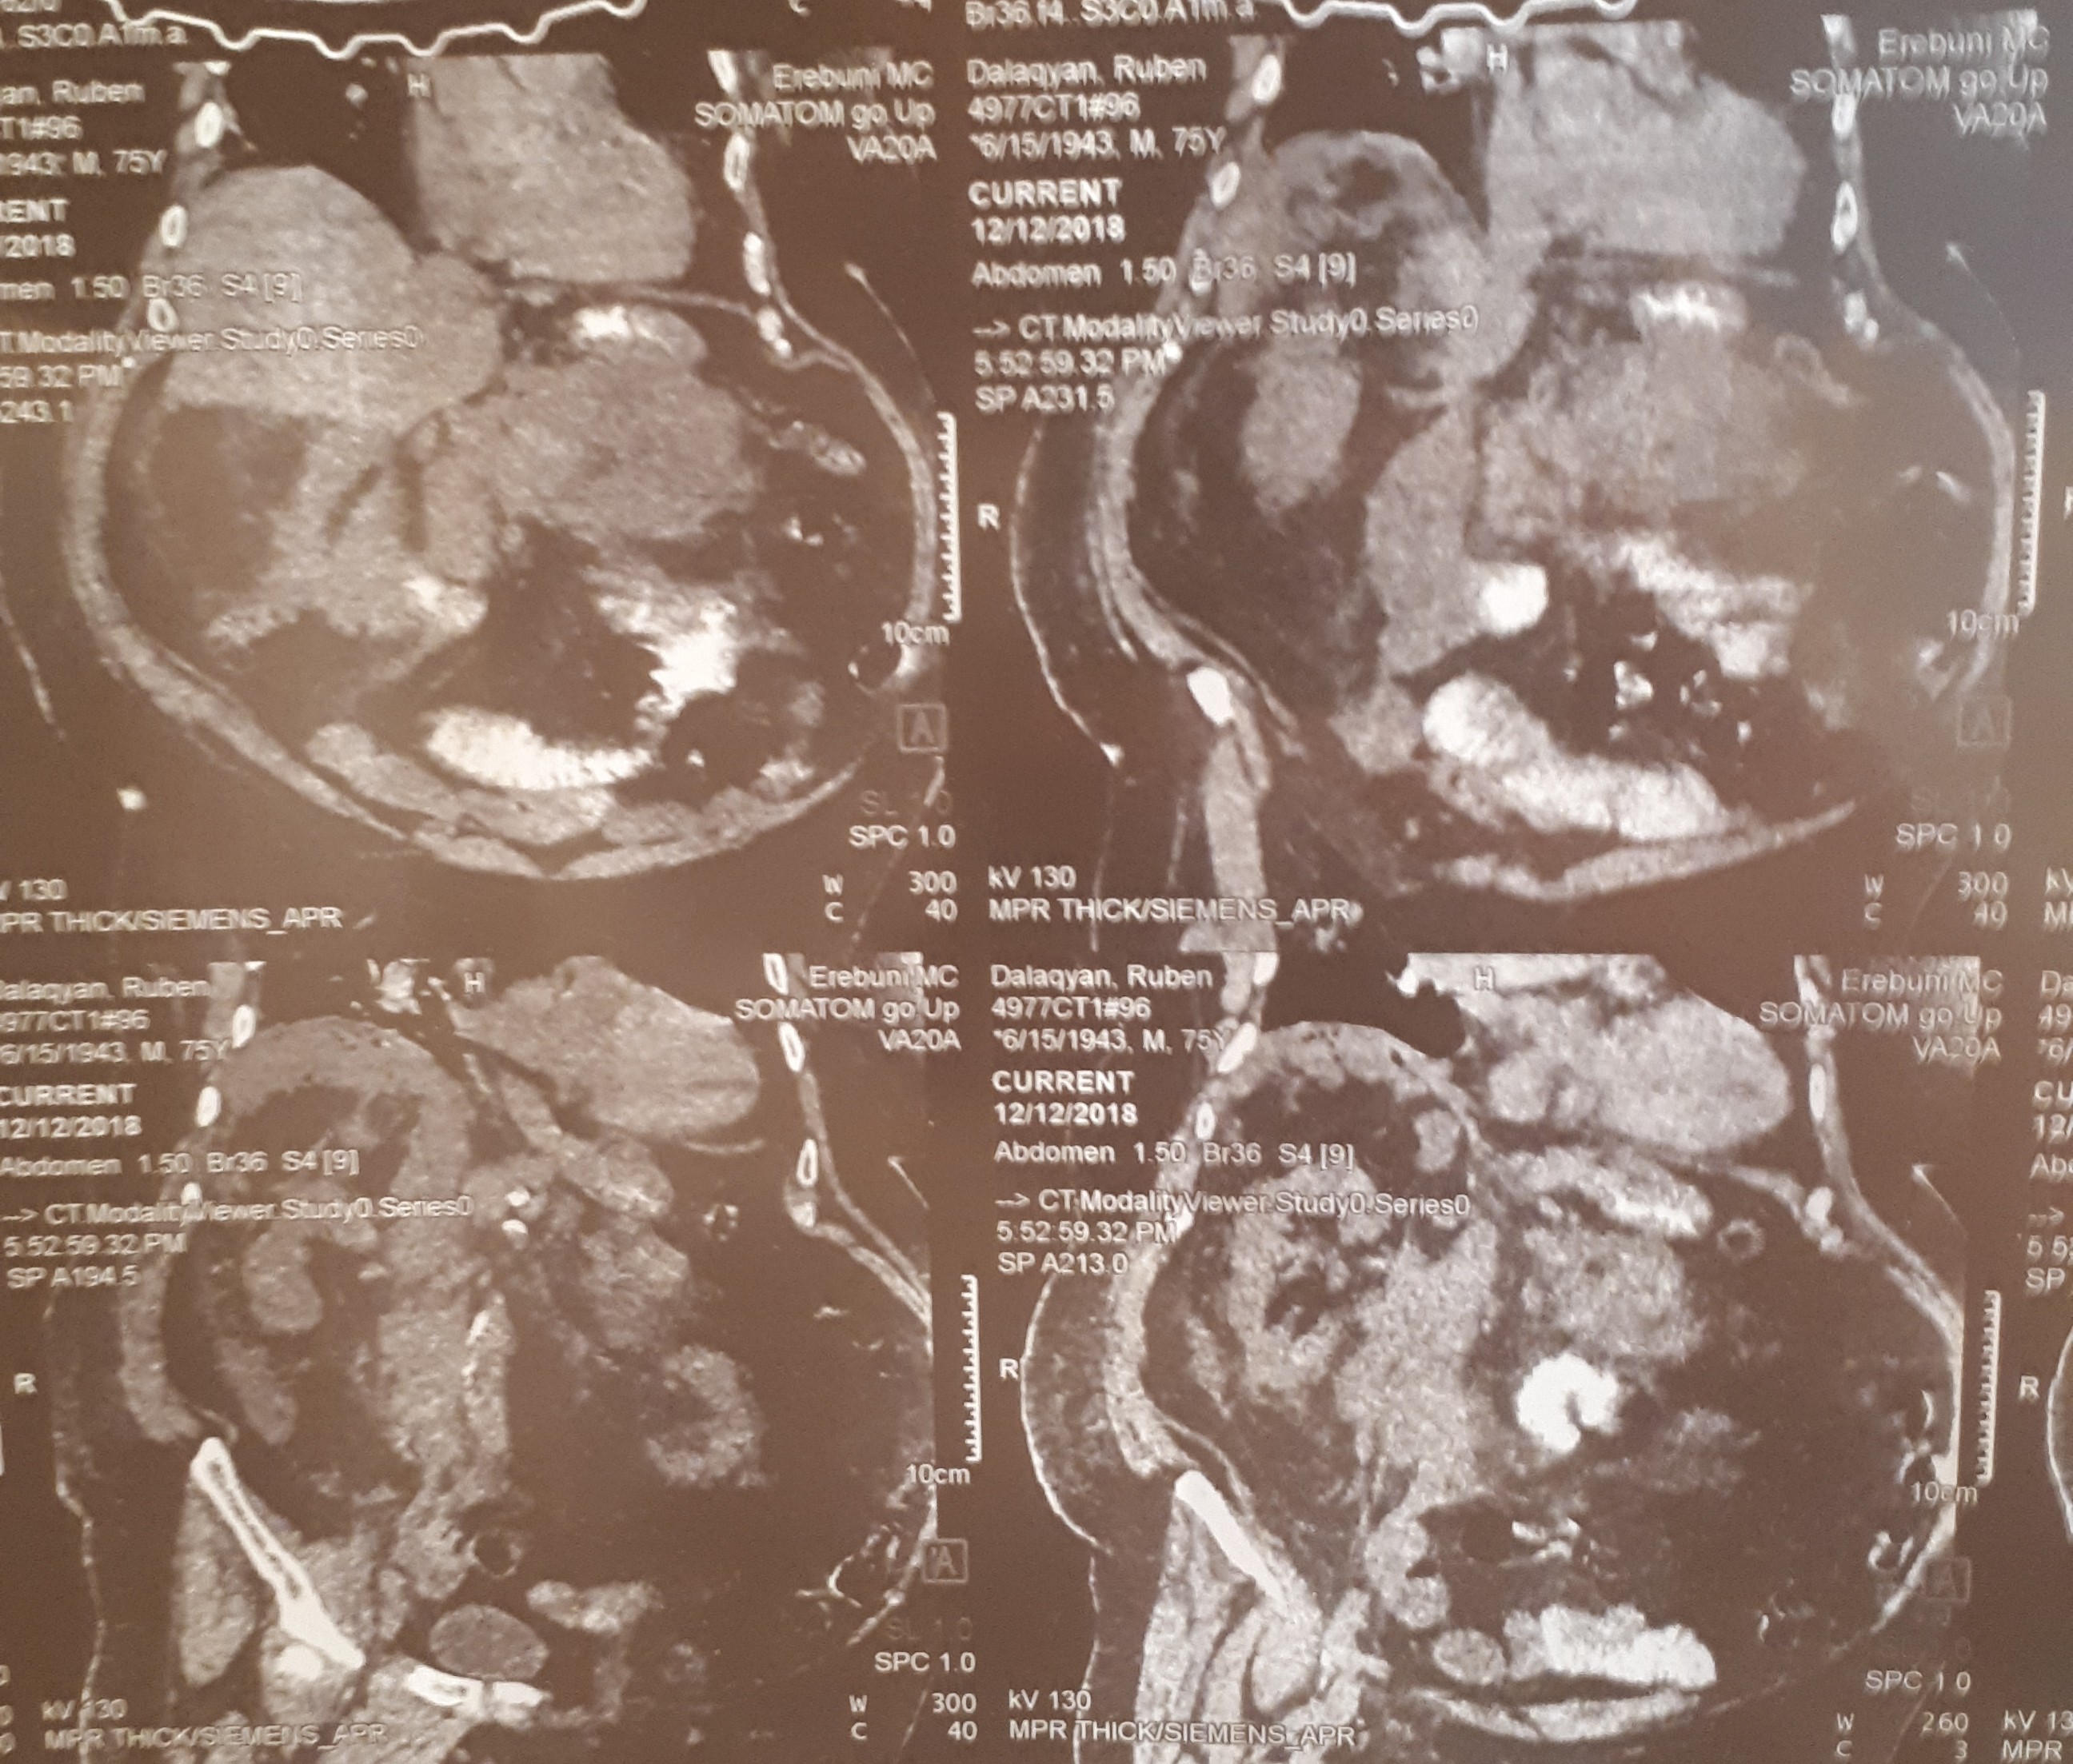

Օրինակ, ՈՒՁ հսկողության տակ դրենավորում կատարել: Առանց կտրվածքների, առանց ընդհանուր անզգայացման: Երեք մեծ թարախակույտ կար, որ հաջողությամբ հեռացրեցինք: Հիվանդը մի քանի օր անց տուն գնաց>>,- պատմում է բժիշկը:

տղամարդը եւ հիպերտենզիա ԱՓՇ-ում…Այս խնդիրների դեպքում բաց վիրահատությունը ուղղակի հակացուցված է: Արա Վարդանյանը ընտրել է այլ ճանապարհ: Առաջին հերթին՝ տեղային անզգայացման պայմաններումուլտրաձայնայինհսկողությամբ իրականացվել է հետորովայնամզային տարածության թարախակույտի դրենավորում, հաջորդ օրը կատարվել է ճարպոնային ծոցի դրենավորում: Սահմանվել է դինամիկ հսկողություն եւ կոնսերվատիվ թերապիա: Ինֆուզիոն, հակաբակտերիալ, սիմպտոմատիկ թերապիան շարունակվել է վիրաբուժական բաժանմունքում: Սրանով, սակայն, բուժումը չի ավարտվել: Մի քանի օր անց դրենավորվել է նաեւ աջից ենթադիաֆրագմալ տարածությունում առկա թարախակույտը: Հիվանդը ստոցիոնարում բուժումը շարունակել է եւս մի քանի օր եւ դուրս գրվել հիվանդանոցից բավարար վիճակում, ճարպոնային ծոցի եւ հետորովայնամզային տարածության գործող դրենաժներով: Նա, իհարկե, կշարունակի մնալբժշկի հսկողության տակ, բայց վերադարձել է նախկին կենսակերպին, ցավային զգացողություններ չունի: